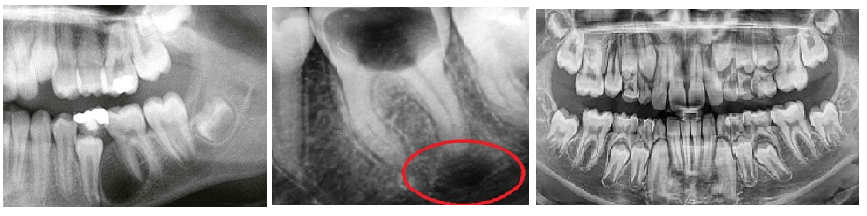

Гранулемы редко превышают 1 см в диаметре. Небольшие гранулемы можно различить только при рентгенологическом исследовании, ортопантомограмме или компьютерной томографии.

Уточнить диагноз помогут инструментальные обследования:

- рентген-снимок;

- радиовизиография;

- компьютерная томография. На рентгене гранулема выглядит как округлое затемненное пятно с четкими контурами.